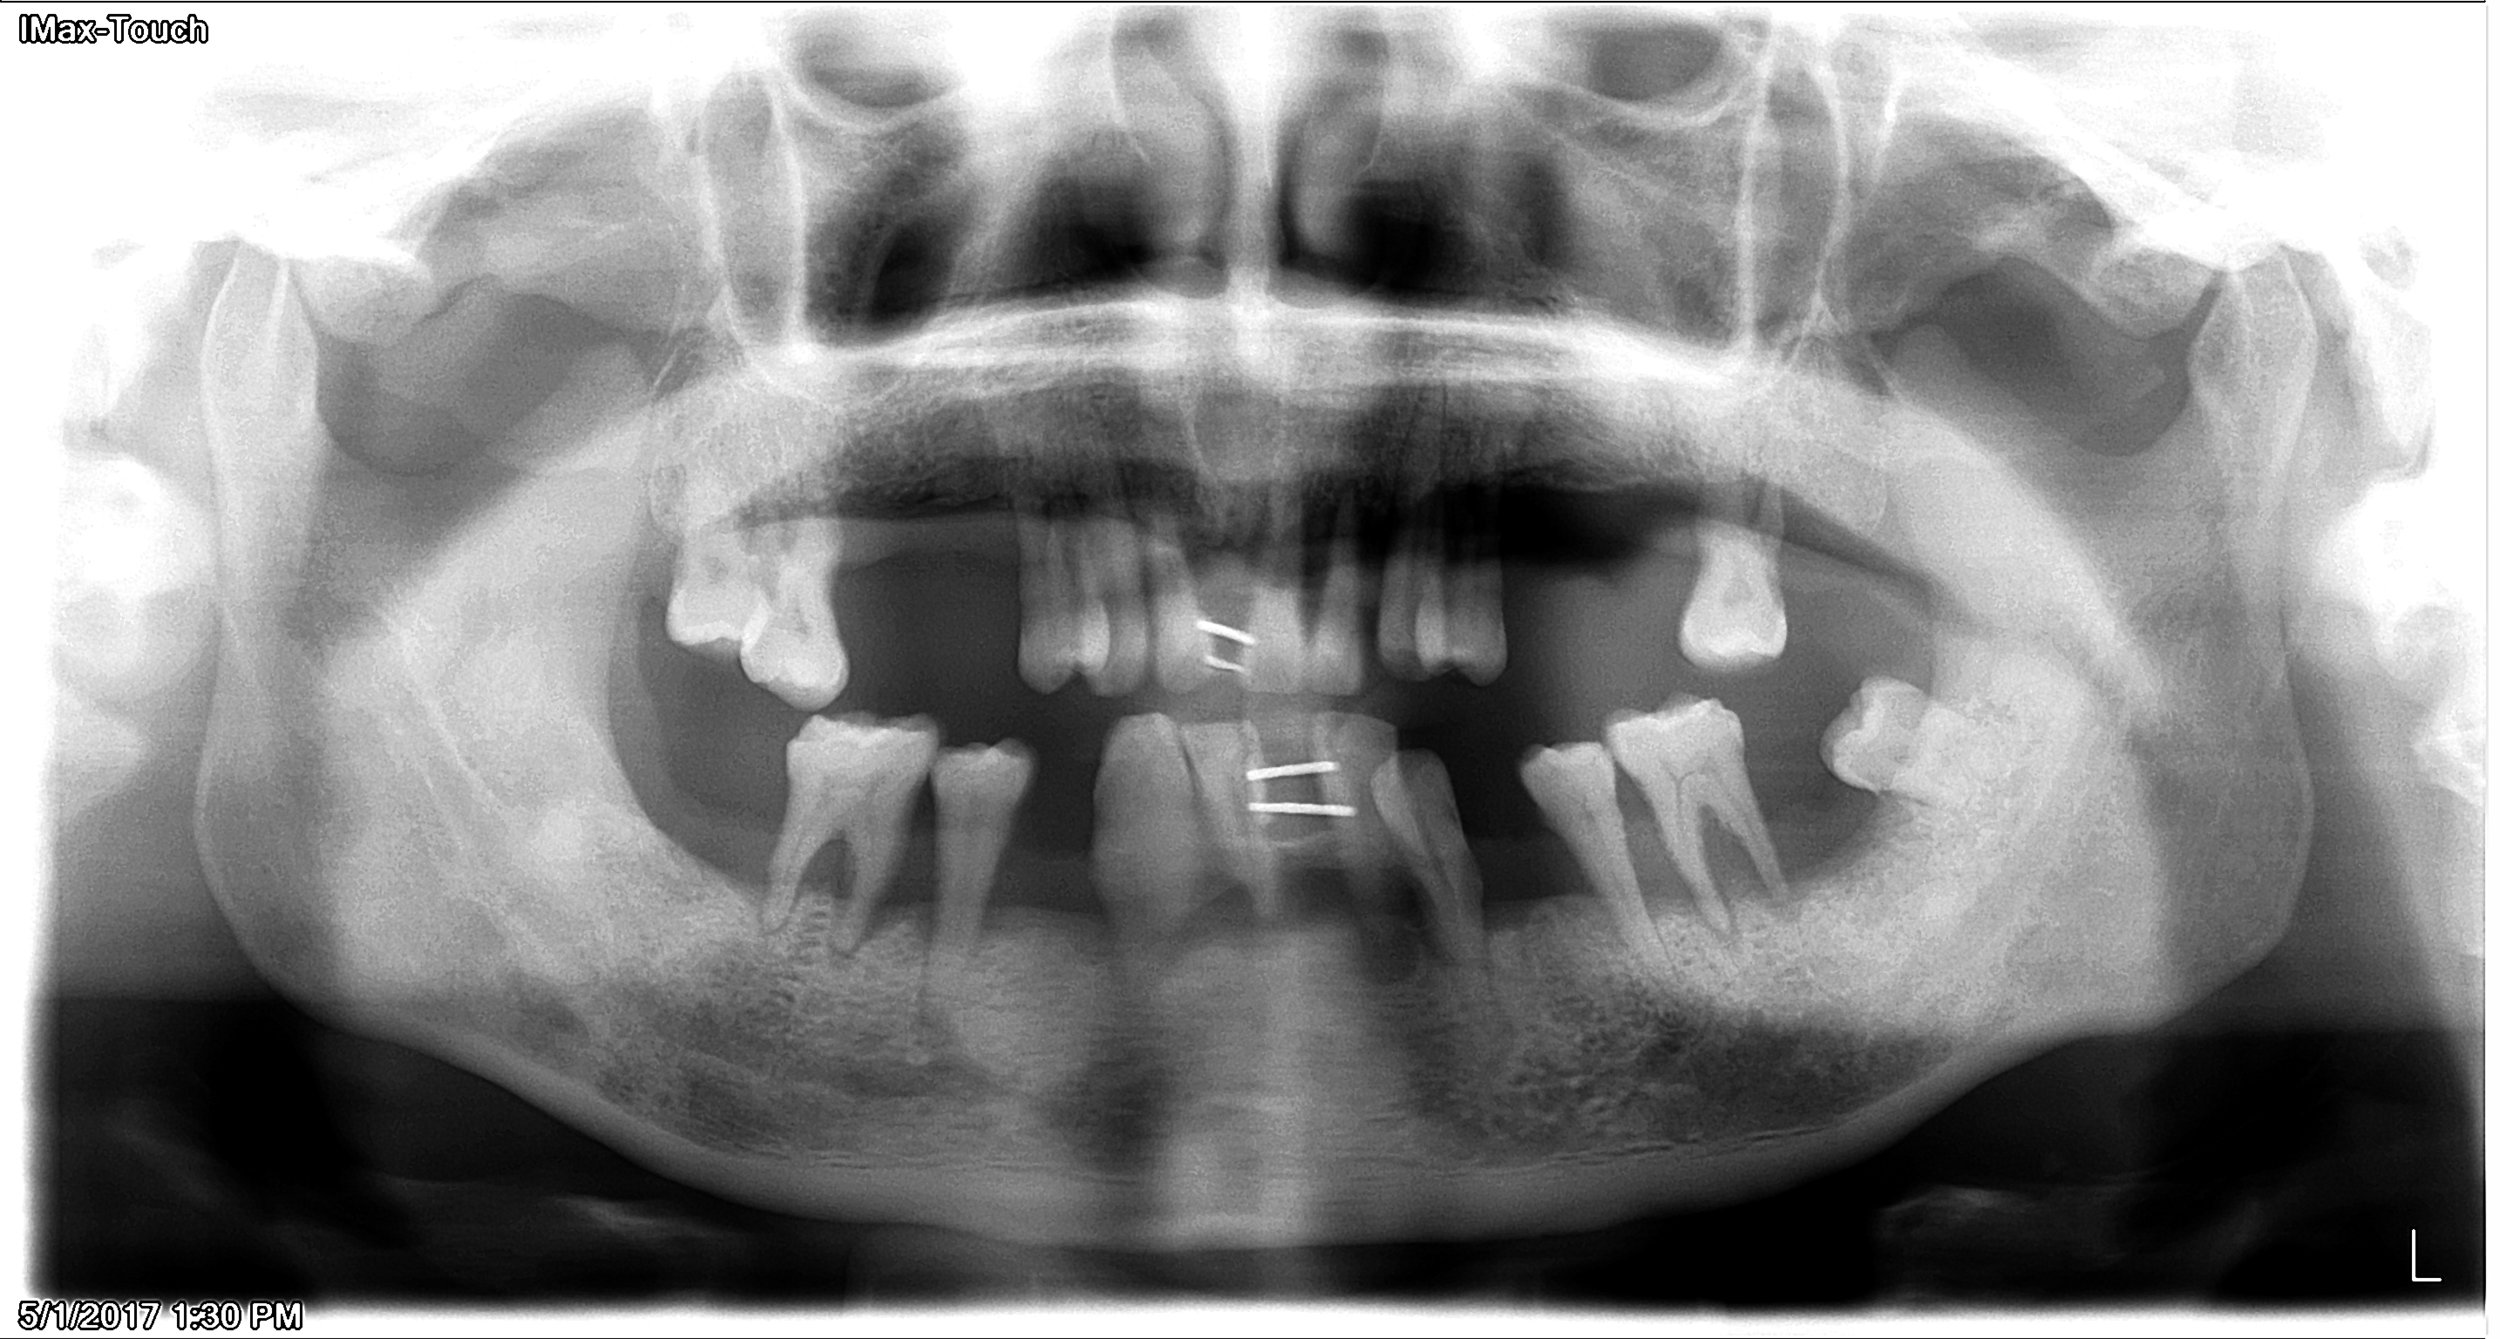

1. Consultation with Dr.Chen. Evaluate medical health and dental conditions. Discuss treatment goals, time frame, number of visits and fees. Surgical appointment is scheduled.

Initial consultations evaluate patients existing teeth and bone.

Panoramic x-ray showing missing teeth in both arches